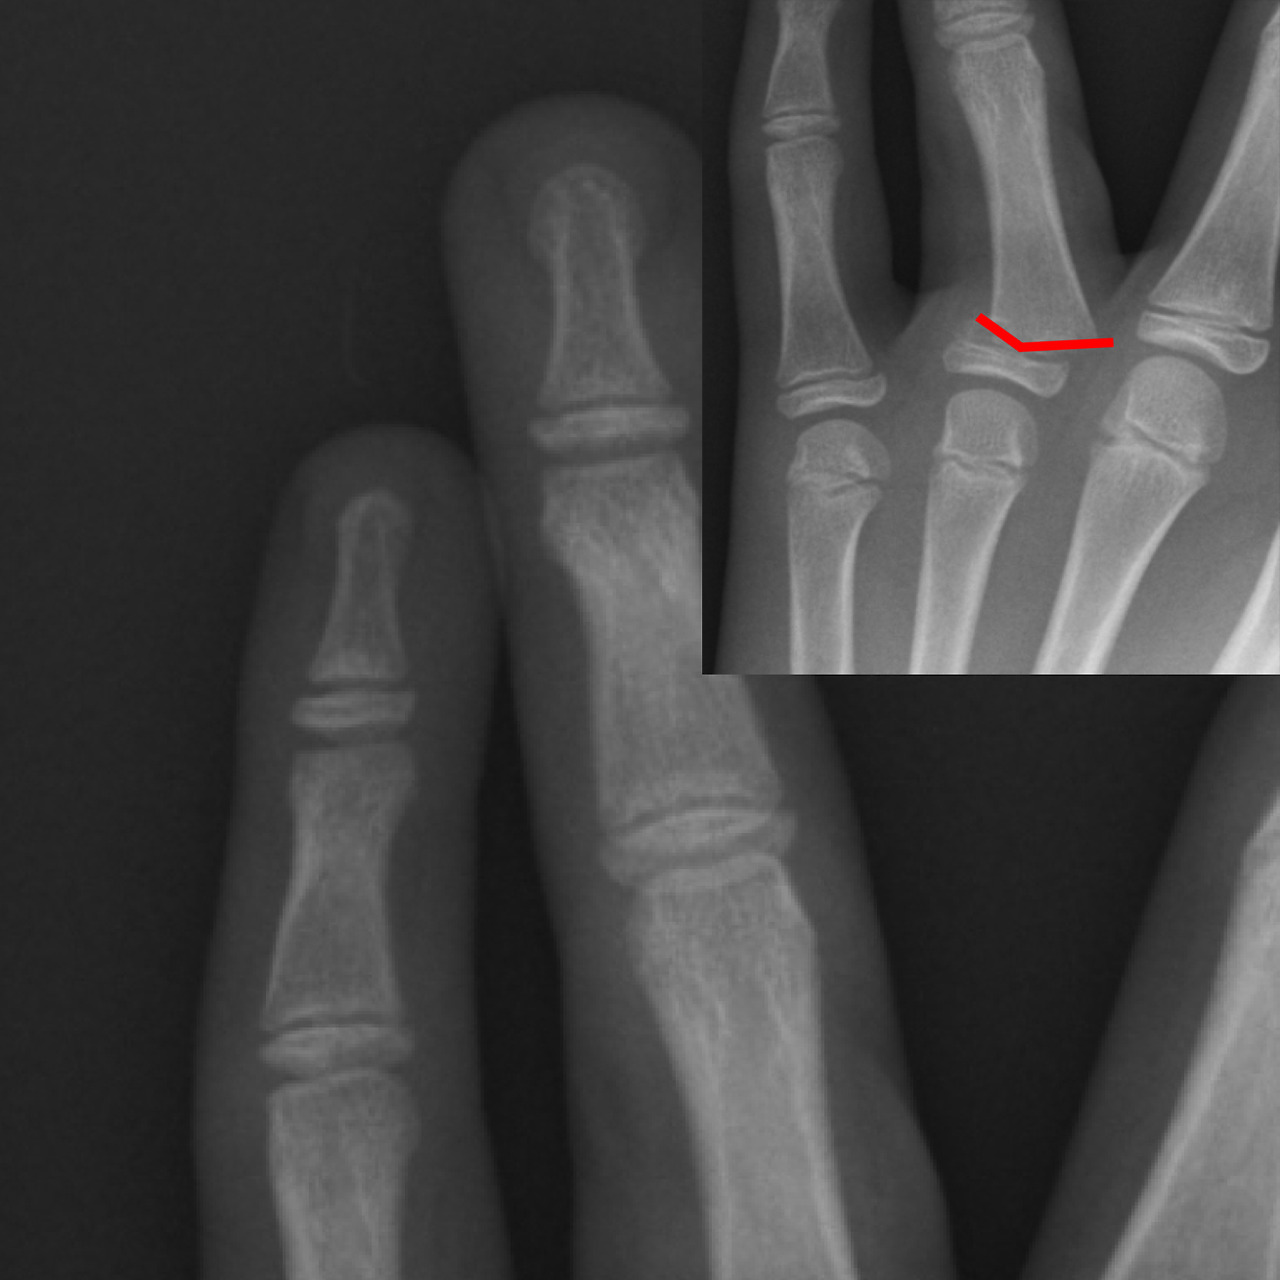

발가락 골절 분류

- 무지(엄지) 골절: 체중 부하가 커서 합병증 위험↑

- 중간지(2–4번째) 및 새끼발가락 골절: 비교적 단순하지만 변형 시 기능 저하

- 피질부(말단) 파열, 간부(몸통) 골절, 관절 내 골절, 스트레스 프랙처 등으로 세분화합니다.

- X-ray 2 방향 촬영이 1차 진단 표준

- 모호할 경우 CT/MRI 추가

- 수술(핀·스크루 고정)

- 변위 2 mm↑, 관절 선 불일치, 개방 골절일 때 선택